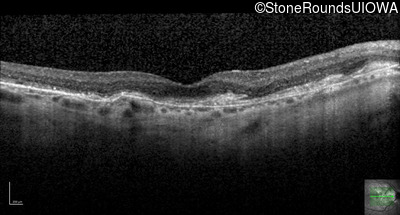

Optical Coherence Tomography - Right - 20/20 -1

Exemplar / OCT Stack

OCT Stack